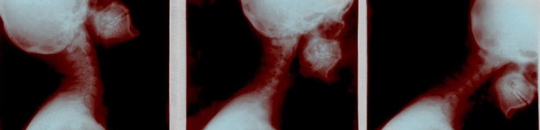

The dangers of neck injury from rear-end collisions are well documented, with many Americans sustaining them every year. This alone should be enough to cause other drivers to pay careful attention to following distances and to maintain safe speeds. Unfortunately, however, these accidents continue to happen. We recently had one such client who was injured in a rear-end collision with a big rig truck, causing recurring neck pain that limited our client’s day-to-day activity at work and home.